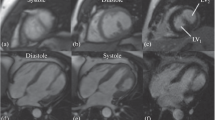

C. Automated segmentation of cardiac ventricular dimensions in MRI

Automated segmentation of the left ventricle in MRI was the first image process algorithm implemented in Segment. The algorithm has been described and validated [5, 17]. There was an excellent correlation between automated segmentation and manual segmentation for end diastolic volume (EDV), R2 = 0.99, with a mean error of -1 ± 11 ml, and left ventricle mass (LVM), R2 = 0.94, with a mean error of 4 ± 15 ml [5]. Tools for semi-automatic delineation of the right ventricle have also been incorporated. From the automatically or semi-automatically segmented surfaces, wall thickness, wall thickening, and fractional wall thickening can be calculated [5, 17]. Typical computational time for a standard Windows XP desktop PC (Intel Dual Core 2 GHz, Buss speed 770 MHz and 2 GB RAM) is about 10 seconds for a typical data set with 12 slices, and 30 timeframes.